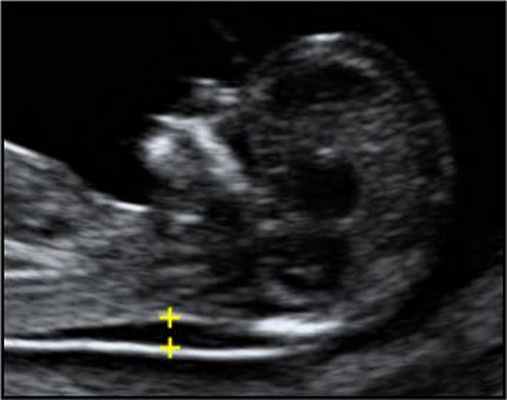

- толщина воротникового пространства (ТВП) – является основным признаком хромосомной патологии у плода. Патологической величиной считается увеличение ТВП больше 95-й процентили для каждого срока гестации. Каждое увеличение ТВП повышает риск существования хромосомной аномалии у плода.

ТВП в норме ТВР при патологии

Важно понимать, что увеличение ТВП - это признак (маркер), но не точная диагностика хромосомных аномалий у плода. Определить наличие синдрома Дауна и других заболеваний у будущего ребенка позволяет только инвазивная диагностика с последующим генетическим анализом.